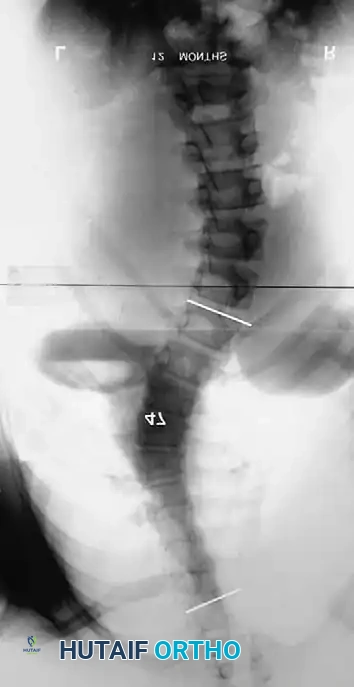

Associated Surgical & Radiographic Imaging

Hutaifortho's Orthopaedic Diagram